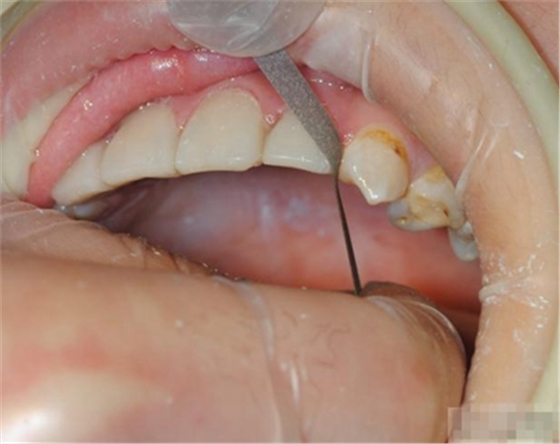

【檢查】12,11,21,22,均行玻璃離子充填,各牙不同程度部分充填物脫落,探(—),叩(—),冷刺激無反應(yīng),無松動(dòng),牙齦顏色粉紅,質(zhì)地堅(jiān)實(shí)而有彈性,點(diǎn)彩正常,牙結(jié)石(—);牙髓活力測試無反應(yīng)。

【診斷】12,11,21,22牙體缺損

選擇合適的完成鉆制備根管,

通常深入到根管的1/2至2/3處